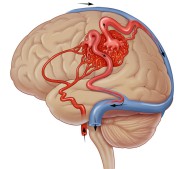

Dat kan met een MRI-scan (Magnetic Resonance Imaging), maar de beste manier om een AVM te ontdekken is een angiografie. Dit is een soort röntgenfoto, maar dan voor je aders. Die zijn op een gewone röntgenfoto niet te zien. Bij een angiografie wordt er een speciale vloeistof in je aders gespoten, waardoor deze wel zichtbaar worden. Dat gebeurt via een katheter, een slangetje dat via de lies of arm wordt ingebracht.